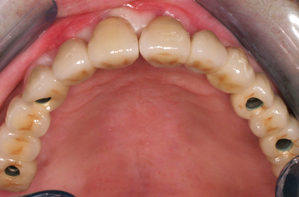

Εμφυτεύματα

Τα οδοντικά εμφυτεύματα ήρθαν για να αλλάξουν τη ζωή μας! Είναι ειδικά σχεδιασμένα για να αποτελούν την υποδομή σε περιπτώσεις αποκατάστασης των δοντιών, για δίνουν την αίσθηση και να έχουν την λειτουργία των φυσιολογικών δοντιών. Αποτελούν μικροσκοπικούς στύλους από τιτάνιο, οι οποίοι εισάγονται στην γνάθο, όπου λείπουν τα δόντια. Τα μεταλλικά τους στηρίγματα λειτουργούν ως υποκατάστατα της ρίζας του δοντιού και τοποθετούνται στη γνάθο μέσω χειρουργικής επέμβασης. Έτσι, ο δεσμός του οστού με το τιτάνιο, δημιουργεί μια ισχυρή υποδομή για τα τεχνητά δόντια, οι ασθενείς χαμογελούν ξανά με αυτοπεποίθηση, ενώ παράλληλα διατηρείτε η δομή του προσώπου τους.

Δείγμα δουλειάς

Πρίν